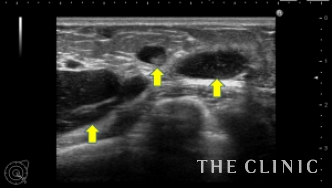

エコーで診てみると、右はほとんど吸収されていますが、左のしこりは最大で5cm以上で、小さなしこりも散在しているのが分かります。

エコーで確認しながら、確実にヒアルロニダーゼ(ヒアルロン酸溶解剤)をしこり内に注入します。注入すると溶解剤とヒアルロン酸が反応して水のような液体になるため、すぐに吸引することができます。